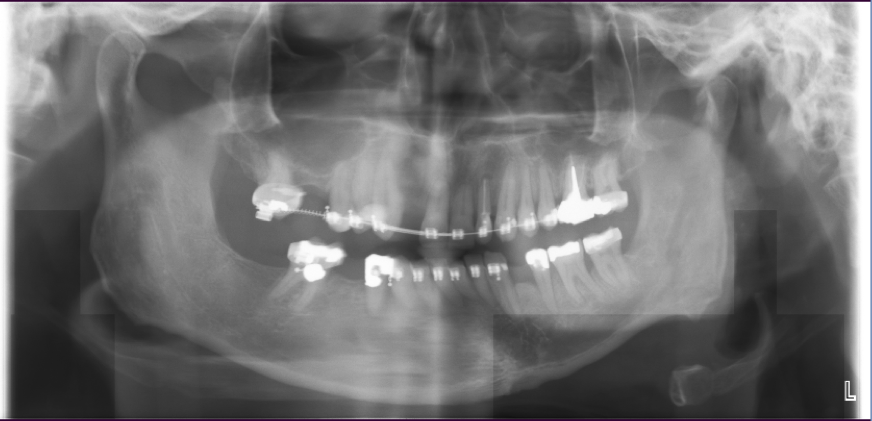

Sinus Lift, Bone Graft, Implants Dr. Noroozi IMPrESS Perio Implant Center

The bone used in a sinus lift may come from your own body (autogenous bone), from a cadaver (allogeneic bone) or from cow bone (xenograft). You will need X-rays taken before your sinus lift so the dentist can study the anatomy of your jaw and sinus. You also may need a special type of computed tomography (CBCT) scan. This scan will allow the dentist to accurately measure the height and width of your existing bone and to evaluate the health of your sinus.